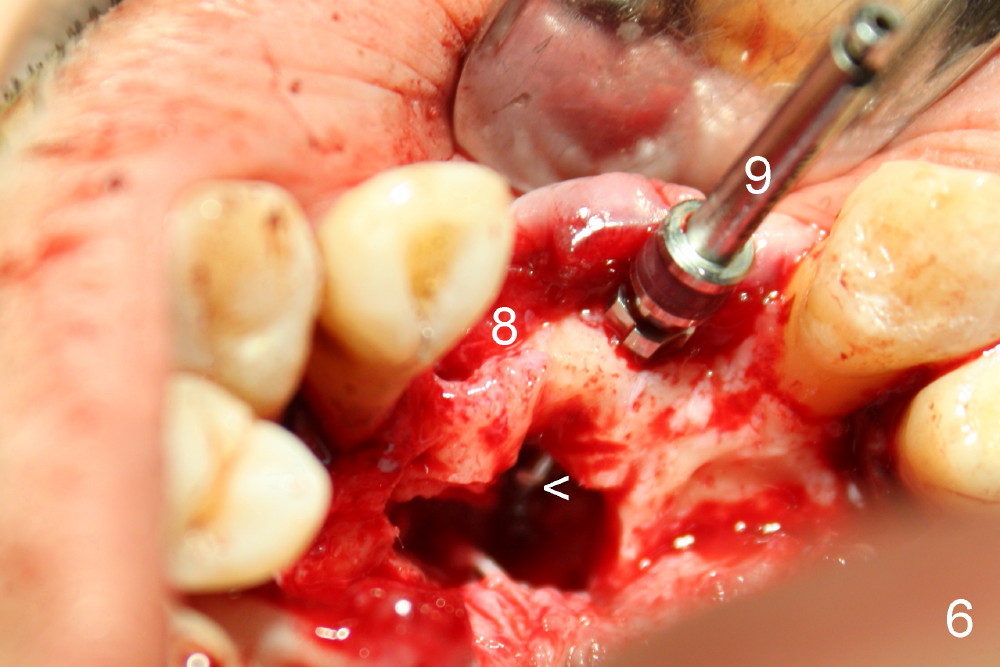

Trajectory is being corrected while osteotomy is increasing with reamers (Fig.4: 3 and 2.5 mm). When a 4.5x20 mm tap is inserted at the site of #8 (Fig.5), it is stable. A 3.5x20 mm tapered drill is at the site of #9 for parallelism. When the tap is removed from the osteotomy of #8, the middle portion of the 3.5x20 mm drill at the site of #9 is seen to pass the socket of the left mesiodens (Fig.6: <).